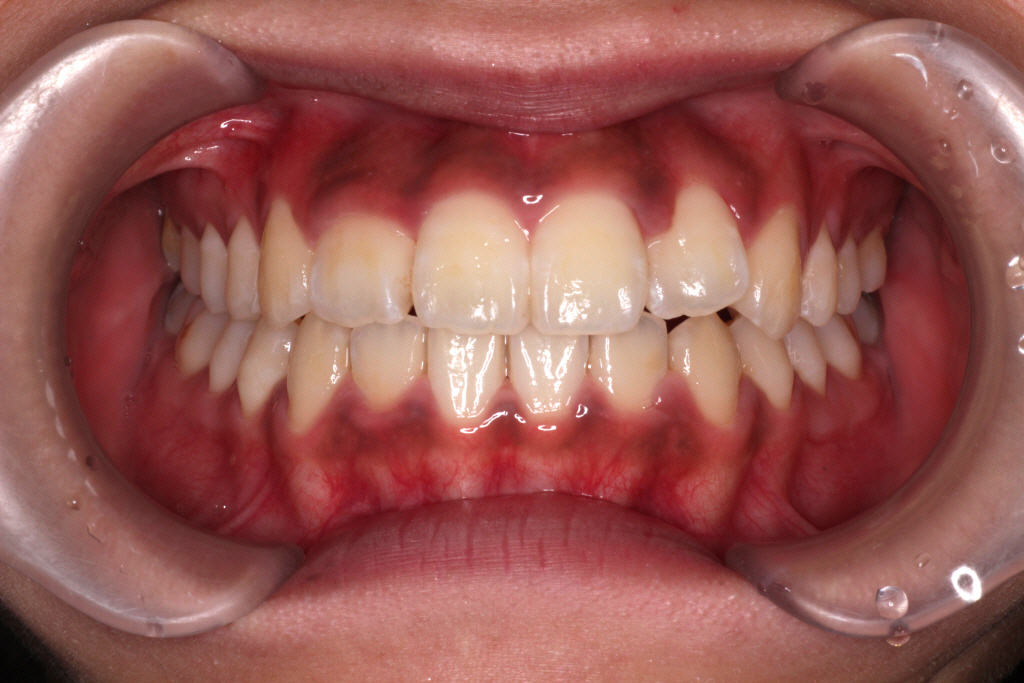

初診時のお口の中の状態です。

上の前から2番目の歯が下の歯列より内側にあり叢生です。

側方の上下の咬合関係が理想の上1本に対して下2本の理想的な噛み合わせではない。

歯列の幅がせまい。

診断:上顎前突・前歯部叢生